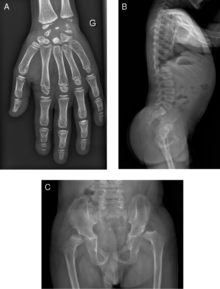

Initially, patients with neonatal or early-childhood onset diabetes are possible candidates for having Wolcott–Rallison syndrome.[1] The other symptoms include the multiple epiphyseal dysplasia, osteopenia, intellectual disability, and hepatic and renal dysfunction.[1] Patients with the symptoms that line up with Wolcott–Rallison syndrome can be suggested for genetics testing. The key way to test for this disease specifically is through genetic testing for the EIKF2AK3 mutation.[7] Molecular genetic analysis can be done for the patient and the parents to test for de novo mutations or inherited. It can also show whether the patient's parents are heterozygotes or homozygotes for the normal phenotype.[4] X-Rays can show bone age in relation to actual age. Typically the bond age is a few years less than the actual in the patients with WRS.[4][5][8][9] Hypothyroidism is rare is WRS patients but can occur.[4]